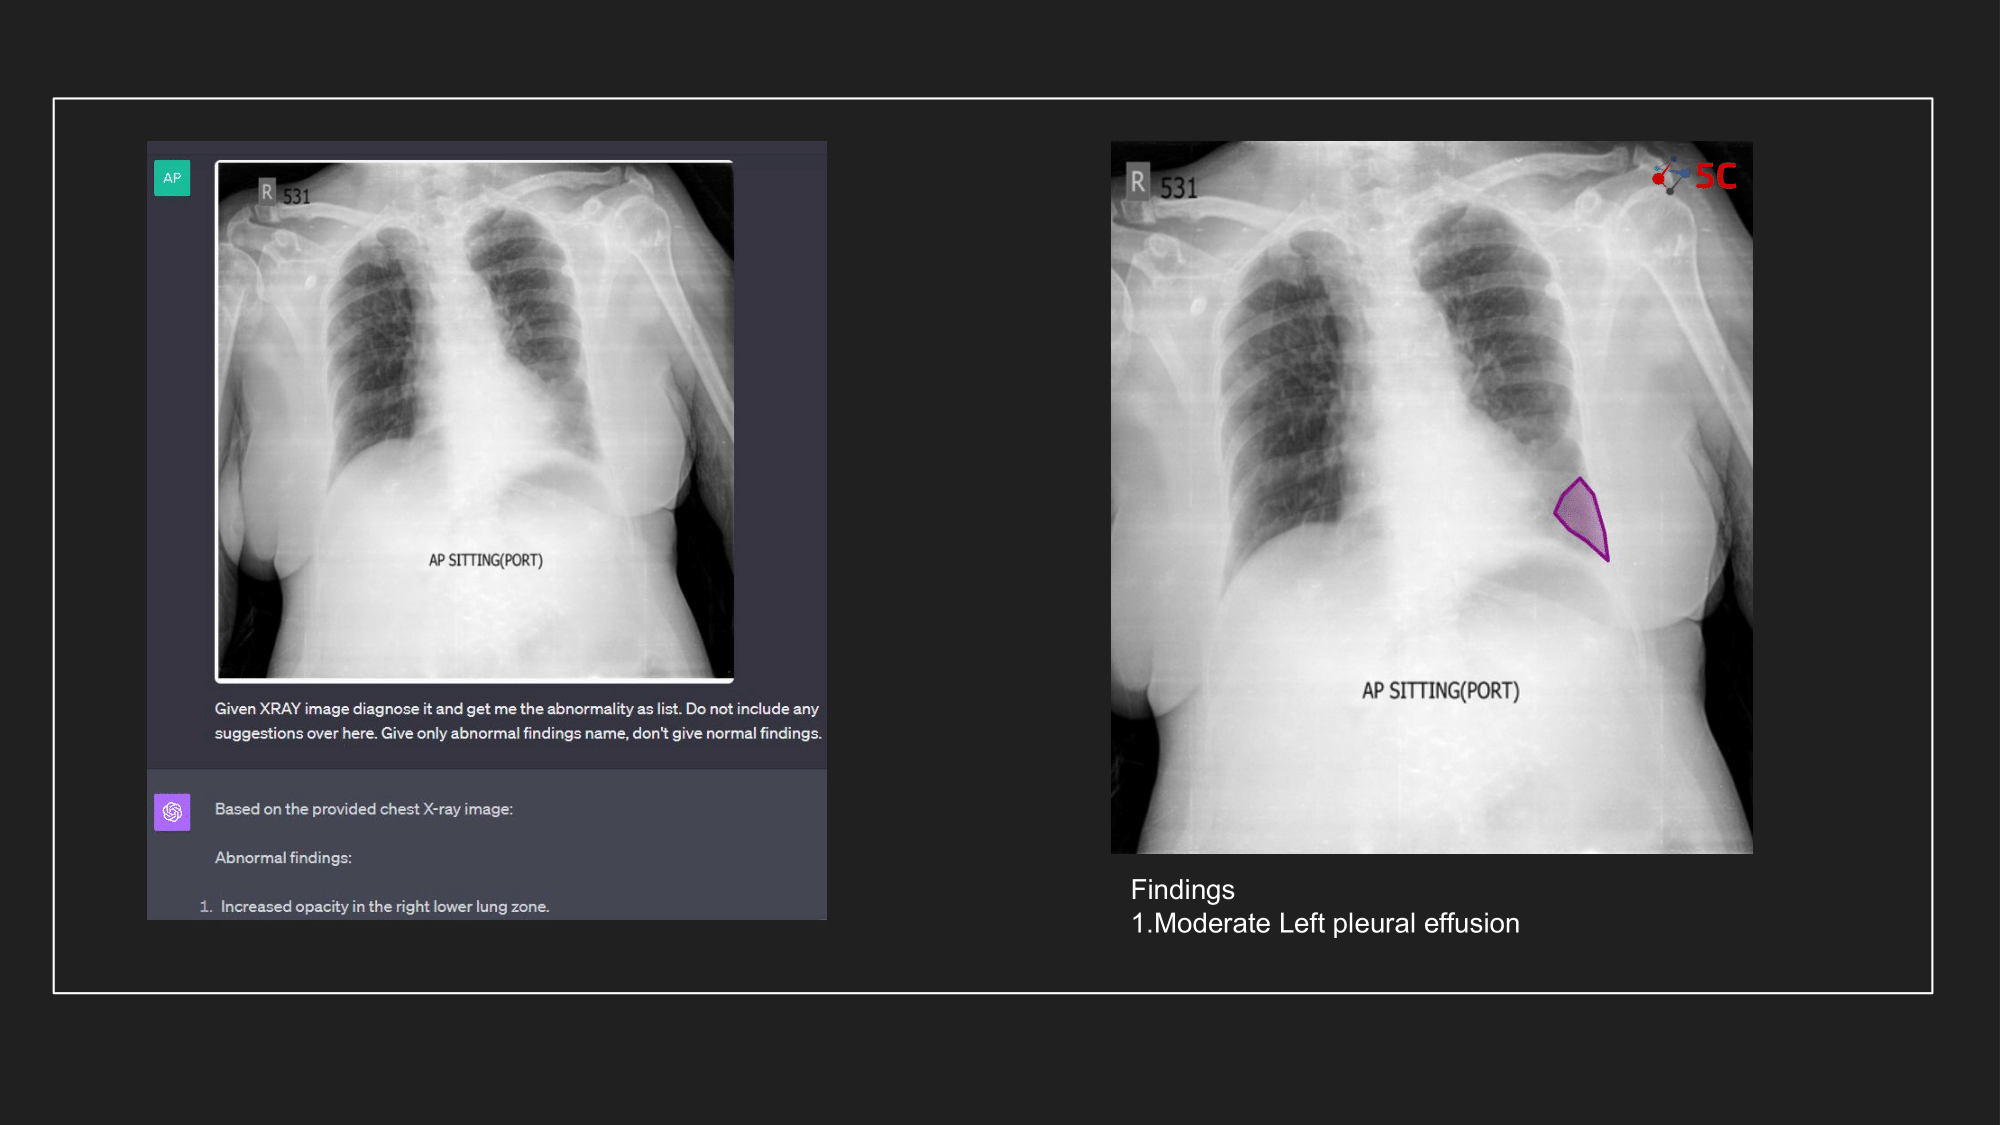

To gauge GPT-4V's prowess in detecting pleural effusion, an experiment was conducted with 10 random chest X-rays known to have pleural effusion. The XRays were sent to GPT-4V, Radiologists as well as to 5C's AI.

Presented below are the results from the experiment.

The output from GPT-4V and from 5C's AI model for the Chest XRays are provided at the end of the post.

At 5C, we are massive believers in the transformative potential of AI in radiology, and our conclusion is that our experiment with GPT-4V and the above radiology images underscores the importance of specialized models. The experiment highlighted that despite GPT-4V's prowess in other domains, it might not yet be primed for radiological applications. That being said, vision transformers as a technology are going to be a key tool in the computer vision stack for AI engineers.

GPT-4V can surely help you fix your bicycle seat, but diagnosing your radiology scan? Not yet, atleast.